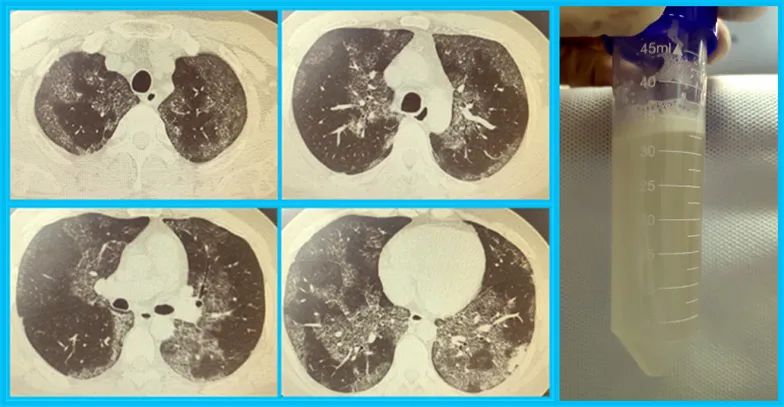

今年32岁的孟先生,1年前出现胸憋、活动后呼吸困难等症状,但是自我感觉还年轻体壮的他一直也没有进行规范治疗。半月前,孟先生呼吸困难、胸憋症状突然加重,爬楼时症状尤为明显。家人多方打听后紧急来到山西白求恩医院呼吸与危重症医学科就诊。入院后,胸部CT显示孟先生双肺弥漫性病灶,呈地图样改变。经支气管镜肺泡灌洗及肺活检术后可见牛乳样灌洗液,静置后分层,风湿系列、肿瘤系列等化验均为阴性。同济医院常驻专家、山西白求恩医院副院长刘先胜教授、呼吸与危重症医学科主任谢敏教授依据患者病史、影像学检查、气管镜检查最终诊断为特发性肺泡蛋白沉积症(PAP)。

7月18日,呼吸与危重症医学科谢敏主任团队在麻醉科王学仁主任团队、中心手术部王秀梅总护士长团队的紧密配合下,对孟先生进行了全麻下经双腔气管插管行右肺大容量全肺灌洗术。麻醉医师一次性完成双腔气管插管置入,并进行漏气检测,成功完成单肺通气要求。谢敏主任将37℃生理盐水分多次经气管插管灌入,再通过重力引流、拍背震荡、反复变换体位将灌洗液引出至玻璃瓶内,直至灌洗液变为清亮。

手术历时3小时18分,8000ml生理盐水分多次灌入,回收7300ml,回收率满意,手术过程顺利。术中患者生命体征平稳,术后拔除气管插管、麻醉苏醒后安返病房。